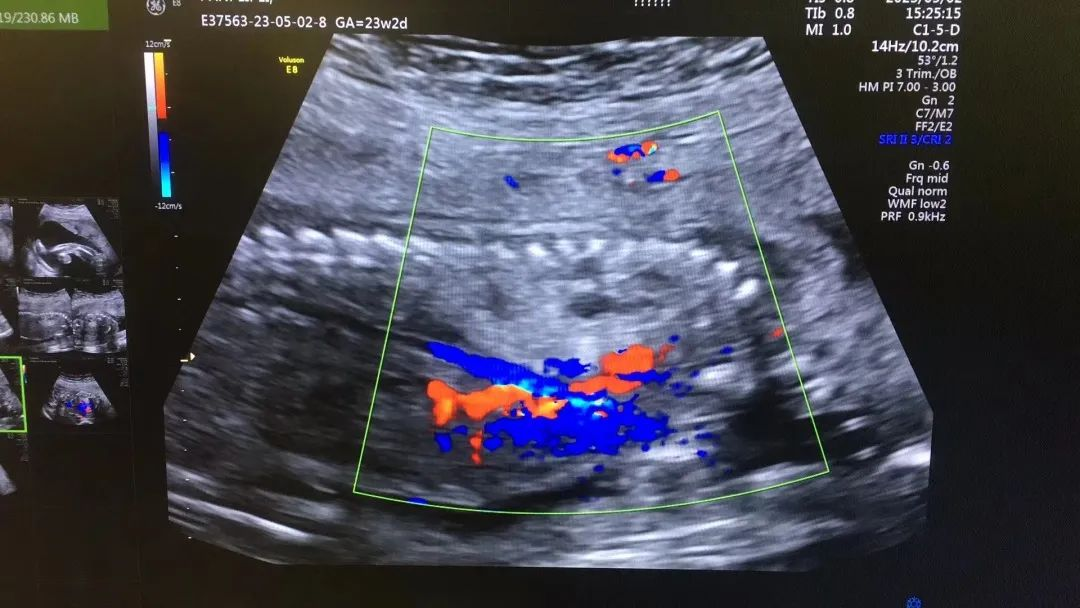

近日,我院超声科医生在给孕中期孕妈做四维彩超检查时,发现胎儿查出异常,孕妈想留下这个宝宝,陷入了两难。

武汉的刘女士(化名),前几个月刚怀上宝宝,全家都特别高兴。怀孕23周+时,刘女士在家人的陪伴下来到武汉仁爱医院超声科做了四维彩超检查,当医生拿出检查报告的时候,刘女士却当场傻眼了,原来,在四维彩超的报告里,诊断出了胎儿右肺囊性腺瘤样病变,她的心顿时揪了起来!

图片36.png

刘女士看到检查结果后,担心该病变会影响腹中宝宝的健康,考虑是否应该终止妊娠。随即,武汉仁爱医院超声科王娟主任为刘女士耐心地解释:先天性肺囊腺瘤是一种肺组织错构畸形,先天性肺囊腺瘤畸形病例约70%的肿块大小较稳定;约20%肿块产前明显缩小或消失;仅10%肿块是进行性增大。单纯的先天性肺囊腺瘤(CCAM)无水肿的胎儿可以密切随访,在28周前接受连续超声复查,CVR<1.6,一般超声动态监测2~4周监测一次,而对于CVR≥1.6的需要在28周前每周1-2次的超声监测,防止出现胎儿水肿,直到分娩。